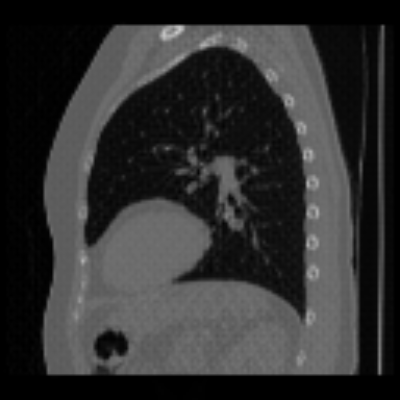

| Axial | Coronal | Sagittal | |

| X2CTGAN | ![]() |

![]() |

|

| DX2CT | ![]() |

| Ground-truth | ![]() |

Figure 3 and Table I(a) using biplanar X-rays show that proposed DX2CT can outperform three existing SOTA methods. Figure 3 shows that DX2CT can provide more accurate overall shapes and details compared to the existing methods. The quality of reconstructed CT slices in the axial plane is less satisfactory than those in the other planes. The reason is that the axial plane is perpendicular to the planes of biplanar X-rays so there exists less spatial (i.e., depth) information in the axial plane. Without using the perceptual loss [33], proposed DX2CT gave comparable LPIPS results with PerX2CTs using [33] in training. Compare their LPIPS results in Table I(a).